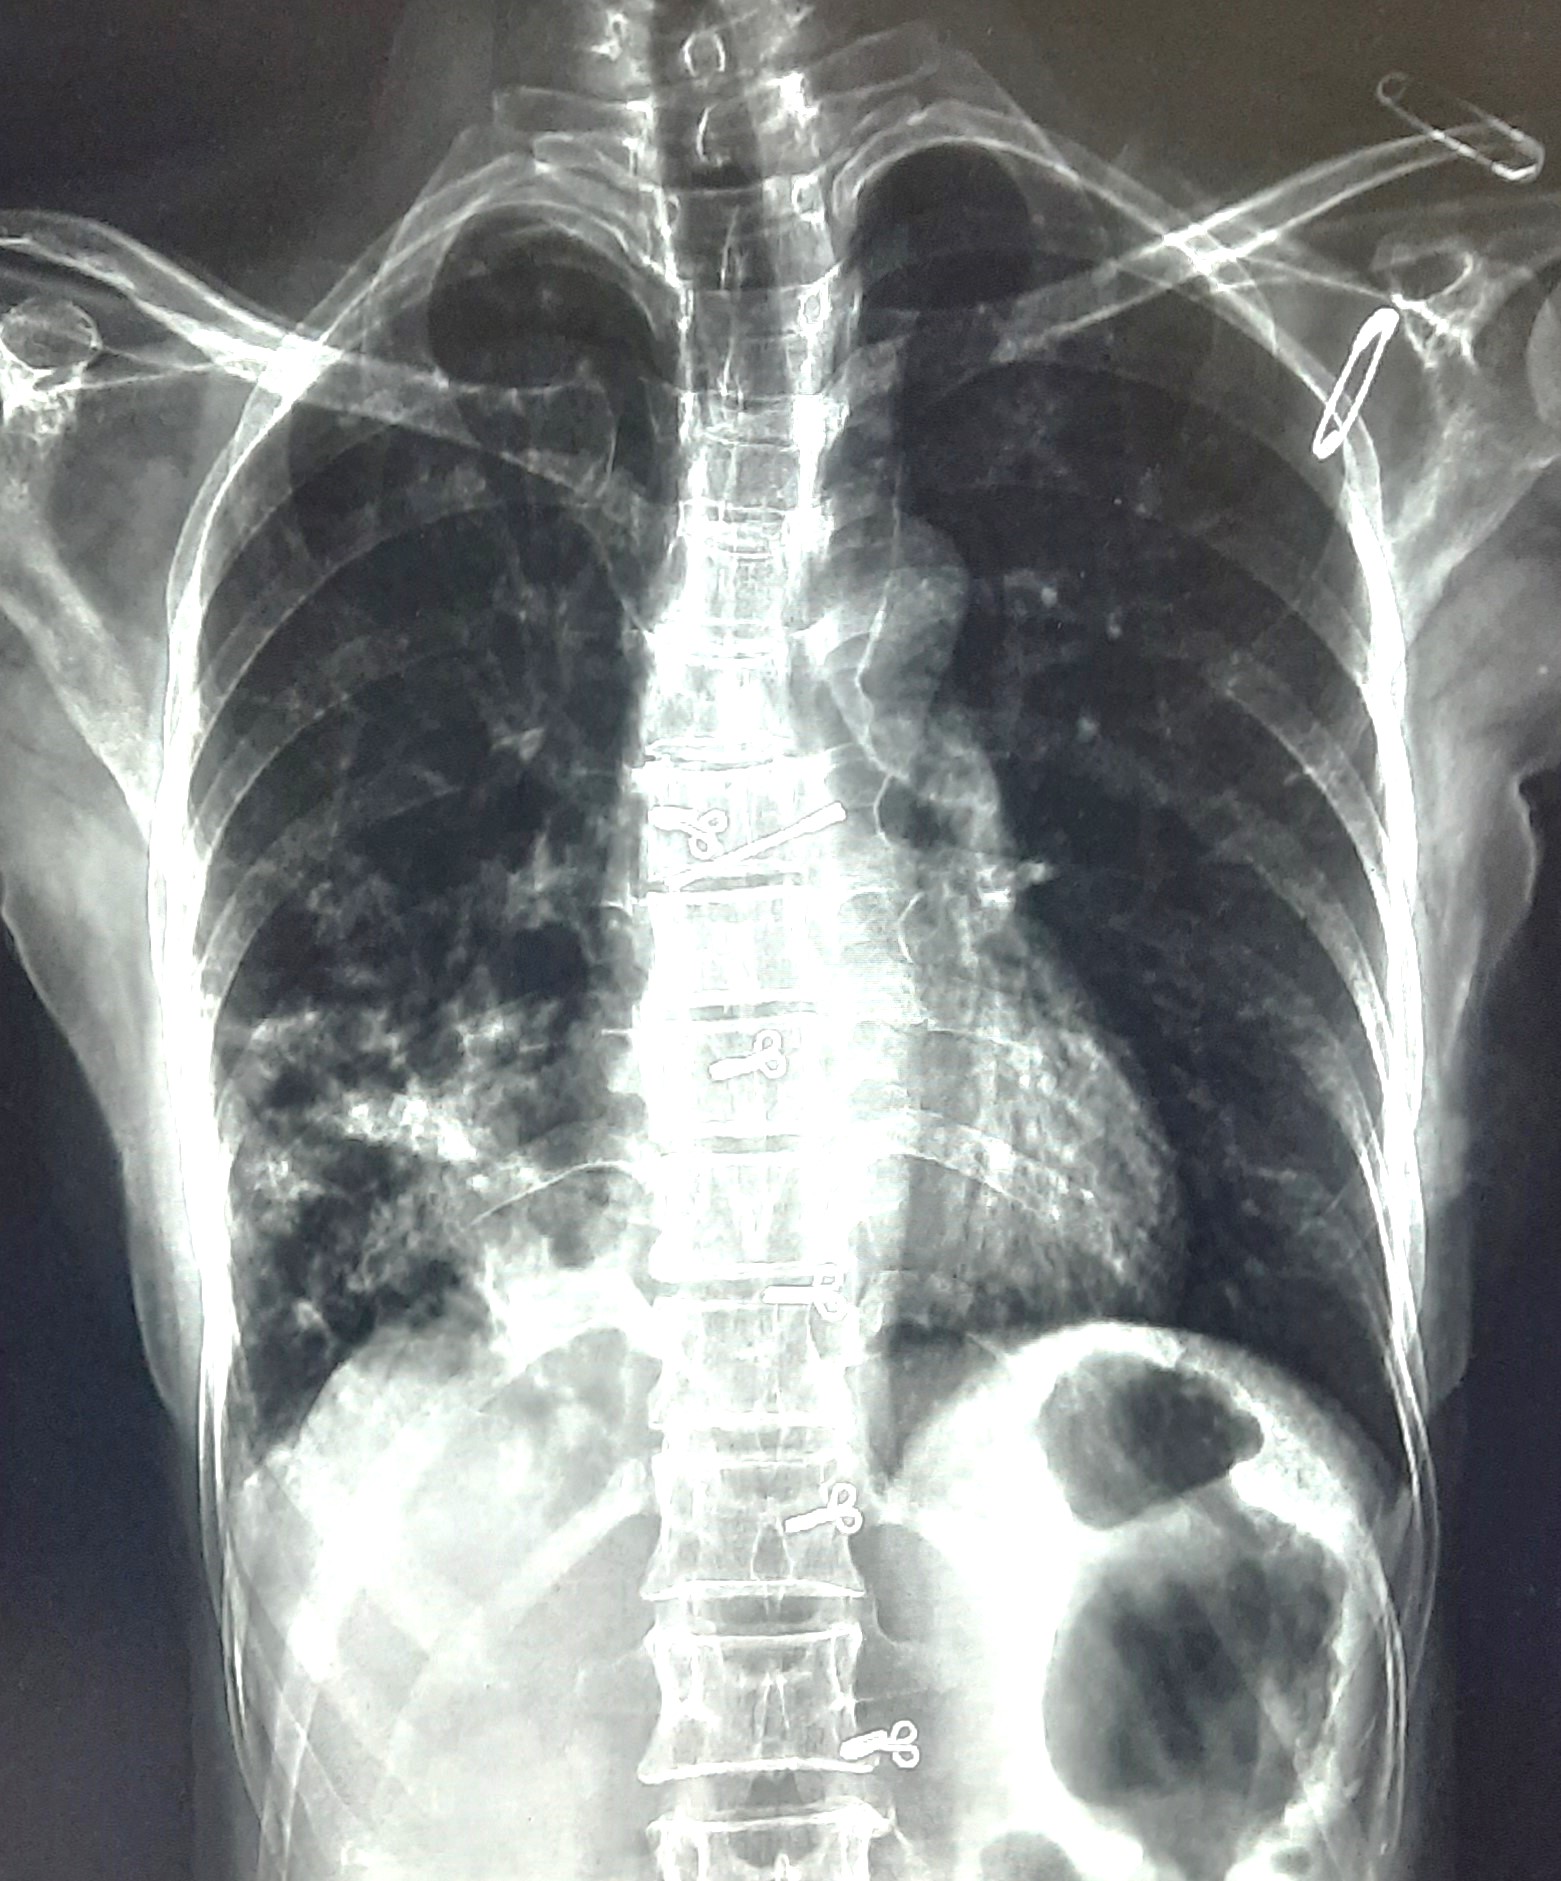

| 53 | IGGMC, Nagpur, Nagpur | P2 | 29-4419 | Rasul Ali | Consent taken on Paper | 36 Yrs. |

Provisional Diag : ?

Final Diag : COPD |

Non-TB Case (Confirmed) | Prominence of broncho vascular markings in bilateral Mid zone il Defined Non-Homogenous Lesion, Changes Of COPD | Abnormality visible on x-ray |